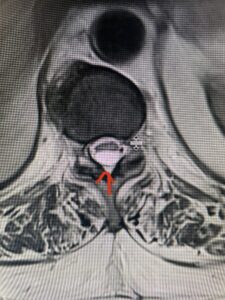

Fig 2a Sagittal and axial T2 weighted cervical MRIs demonstrating large C4 5 herniated disc with spinal cord compression red arrows

This 47-year-old male who four months prior was lifting weights developed sharp pain in his neck. After that he developed progressive numbness in his arms, neck pain and headache. He said that the right arm was worse than the left. On examination the patient had long tract weakness on the right side which included his triceps, finger extensors, hip flexors, and dorsiflexors. The patient did not have hyperreflexia. MRI (Fig. 2) demonstrated a massive, extruded disc herniation with severe cord compression. The patient because of progressive myelopathy and spinal cord compression was indicated for anterior cervical discectomy and fusion at C4-5 (Fig. 3). Patient had significant improvement of weakness and numbness post operatively.

Fig. 2a Sagittal T2-weighted cervical MRI demonstrating large C4-5 herniated disc with spinal cord compression (red arrow)